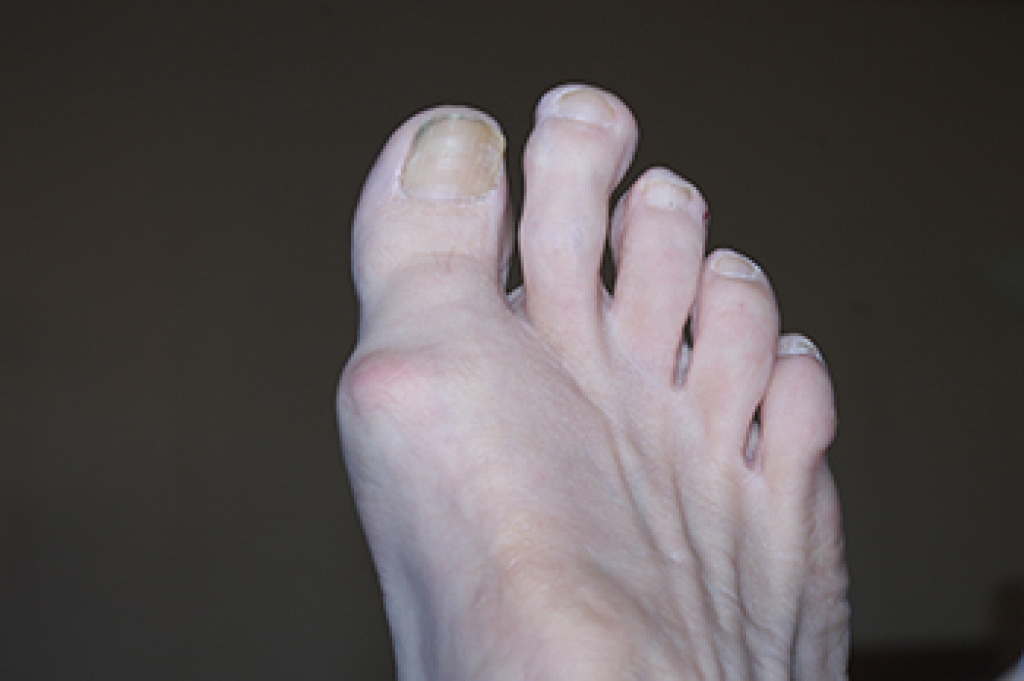

Morton's toe is a foot condition where the second toe is longer than the big toe due to a shorter first metatarsal bone. This structural difference can alter weight distribution, placing extra pressure on the ball of the foot. Causes of Morton's toe are primarily genetic, as the condition is inherited. This imbalance can lead to foot problems like calluses, metatarsalgia, and improper arch support. It may also contribute to pain in the ankles, knees, and lower back due to changes in walking mechanics. Relief options include wearing shoes with proper arch support, using orthotic inserts, and choosing footwear with a roomy toe box. If this condition is causing you discomfort, it is suggested that you consult a podiatrist who can guide you on relief options, including stretching and strengthening exercises that can help improve foot stability.